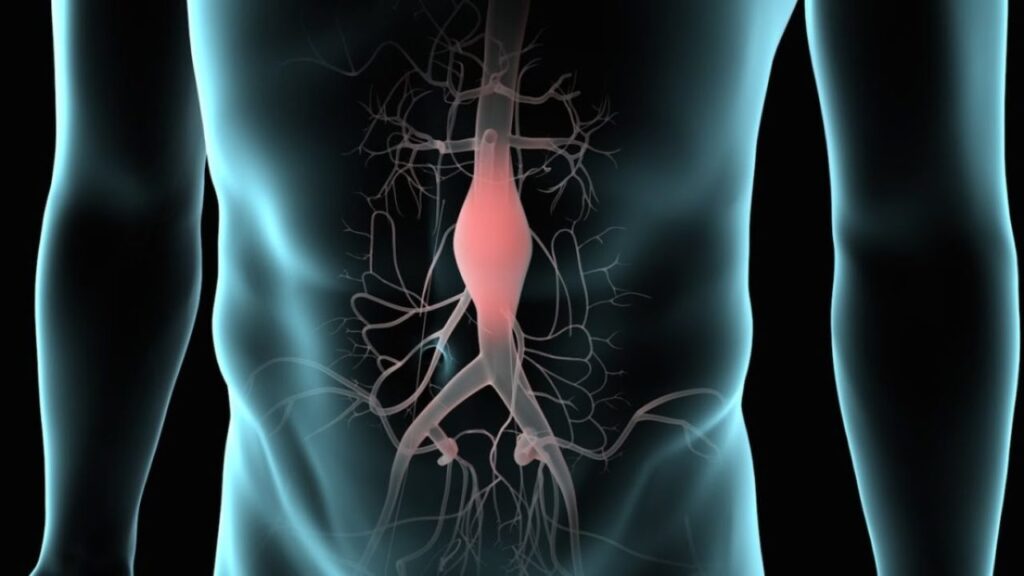

Η Αντιδημαρχία Κοινωνικής Πρόνοιας του Δήμου Ελασσόνας, σε συνεργασία με το Ελληνικό Διαδημοτικό Δίκτυο Υγιών Πόλεων (ΕΔΔΥΠΠΥ), διοργανώνει μέσω του ΚΕΠ Υγείας δράση ενημέρωσης και πρόληψης με θέμα: «Ανεύρυσμα Κοιλιακής Αορτής: Έγκαιρη Διάγνωση – Σωτήρια Παρέμβαση» και η συμμετοχή είναι δωρεάν και ανοιχτή σε όλους τους πολίτες.